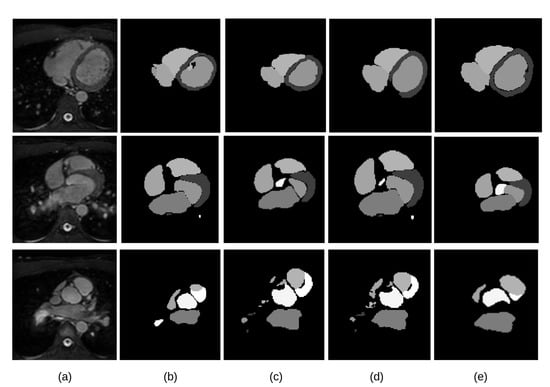

The visual inspection of the obtained segmentations using each network investigated in this work is presented in Figure 10 for the CT dataset, and Figure 11 for the MRI dataset. For example, Figure 11d shows clear improvements regarding LV segmentation that is obtained using FM-Pre-ResNet compared to missed segmentation of LV parts while using Pre-ResNet without a proposed feature merge residual unit as shown in Figure 11b. Moreover, Figure 11e shows a significant reduction in segmentation error compared to all other presented networks. This further highlights the benefits of the proposed FM-Pre-ResNet + VAE approach. Nonetheless, in both modalities, PA and Myo’s segmentation results are significantly lower than other substructures due to high shape variations and heterogeneous intensity of blood fluctuations. Figure 12 shows 3D visualization of the best and the worse segmentation cases on the CT and MRI test dataset obtained using the proposed FM-Pre-ResNet +VAE approach.

Figure 10.

Comparison of the results of four different network architectures. (a) the input original CT image; (b) segmentation results of Pre-ResNet without VAE; (c) segmentation results of Pre-ResNet with VAE; (d) segmentation results of FM-Pre-ResNet without VAE; (f) segmentation results of proposed FM-Pre-ResNet with VAE obtains the most accurate results on the testing dataset.

Figure 11.

Comparison of the results for four different network architectures. (a) the input original MRI images; (b) segmentation results of Pre-ResNet without VAE; (c) segmentation results of Pre-ResNet with VAE; (d) segmentation results of FM-Pre-ResNet without VAE; (f) segmentation results of the proposed FM-Pre-ResNet with VAE obtains the most accurate results on the testing dataset.